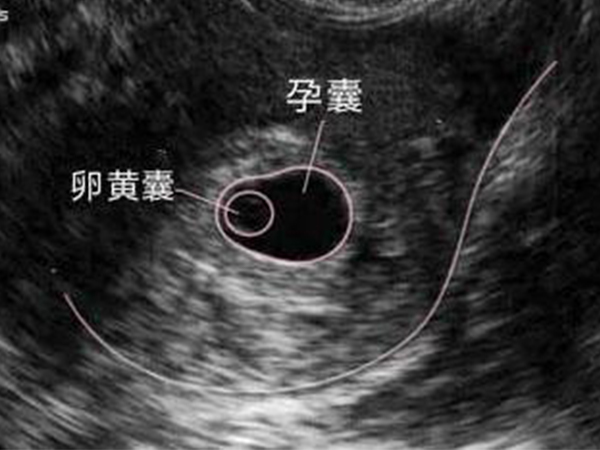

相信对于很多怀孕的妈妈来说孕囊和卵黄囊并不陌生,只是这二者的区别很多人都分不清,其实这二者都是胎儿发育的两种组织形式,通常孕囊比卵黄囊更早被发现,而卵黄囊位于孕囊内,是一种胚胎组织,如果没有卵黄囊,那么孕囊就是一个空壳,而孕囊则是一种妊娠组织,没有这二者中的任何一个,胚胎都无法正常发育成胎儿。

1、发现时间不同,孕囊一般是怀孕5周做B超被发现,而卵黄囊一般是7周左右被发现;

2、卵黄囊是胚胎组织,而孕囊是妊娠组织,没有卵黄囊的孕囊就是一个空壳,为受孕失败,需要终止妊娠;

3、孕囊在外,卵黄囊在里,卵黄囊是位于孕囊内部的胚胎组织,是孕囊的一部分;

4、卵黄囊是指包裹卵黄的一个结果,主要能够分化出各种器官和组织,而孕囊是孕早期整个胚胎的组织成分,孕囊会分化出早期的羊水。

5、卵黄囊是早期孕囊的标志,它是用来判断孕囊是否正常。